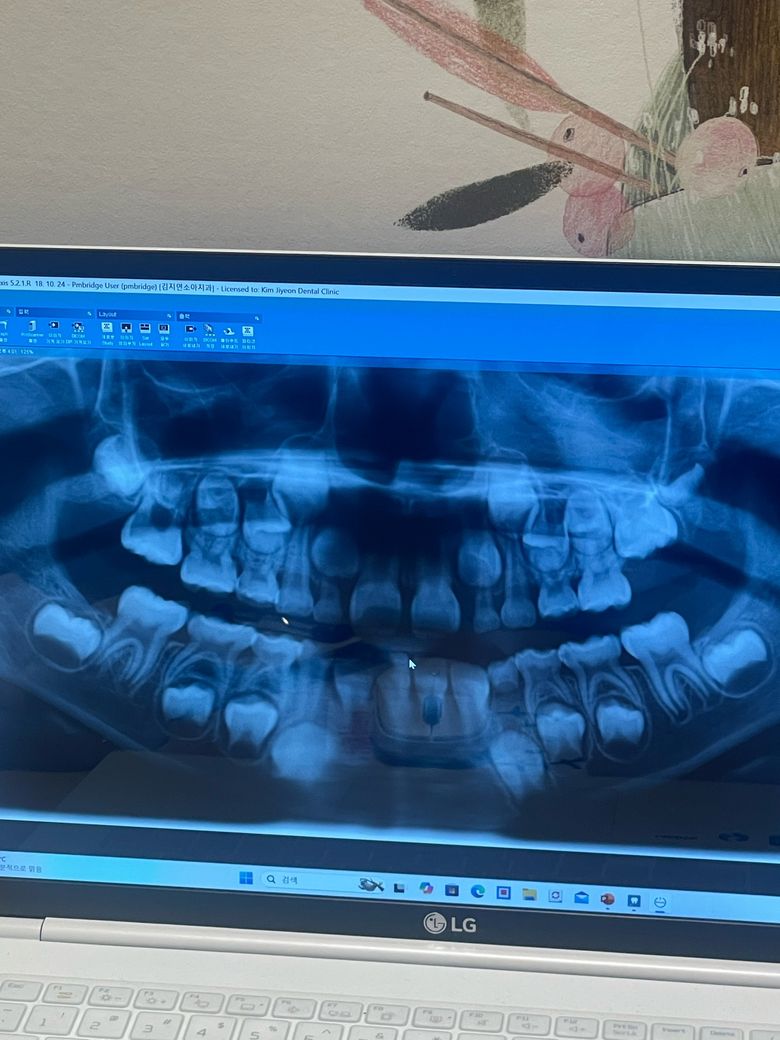

안녕하세요. 아이가 지난 3월 엑스레이 사진에선 괜찮았는데 7월경 살짝 송곳니가 흔들려서 사진을 찍으니 아랫니 4번 영구치가 나면서 송곳니 유치 뿌리를 녹이고 있다고 했습니다. 공간유지장치가 필요할 수 있으니 빠질 것 같으면 바로 내원 하라고 했습니다.

사진상으론 유치 송곳니가 많이 녹아있는 모습이 보여지고 있네요 피도 나고, 많이흔들리면 언제 빠져도 이상하지 않으나 하방 영구치 송곳니는 아직 나오려면 1년 정도 시간은 걸릴 것으로 보입니다

그대로 둔다면 그 옆 치아가 먼저 나오면서 앞으로 쓰러지면서 공간을 닫을 수도 있으나 그건 가능성의 문제입니다

현 상황에서 B&L 장치 하기엔 설명 들으신 것처럼 다소 불편할 것 같네요

그냥 이상태에서 유치 송곳니가 버틸때까지 버티다가 빠지면 그대로 두고 공간이 나중에 부족하면 공간 확장장치를 해주는 방법도 있습니다